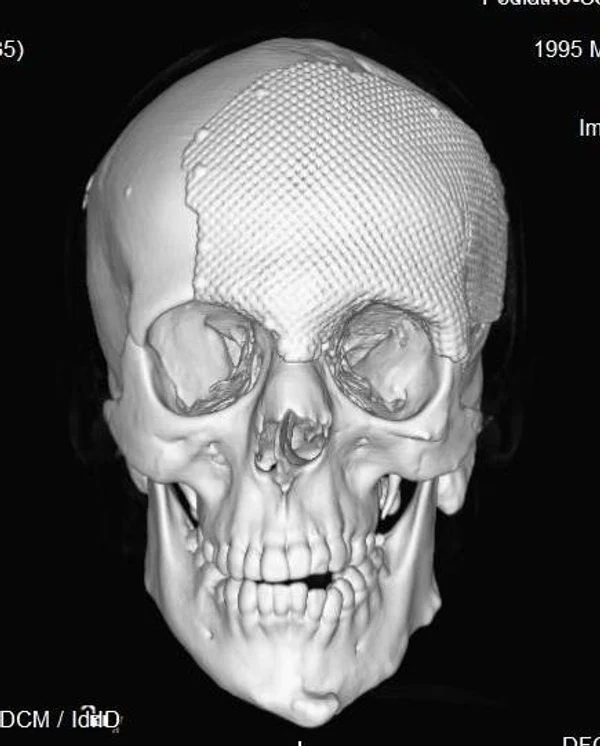

Удаление опухолей черепаВ качестве примера лечения пациентов с опухолями черепа привожу личное наблюдение пациента грудного возраста с опухолью черепа. В возрасте 1 мес. у ребёнка в затылочной области слева родителями обнаружено плотное образование диаметром 5 мм. За 3 мес. до госпитализации образование значительно увеличилось в размерах. При поступлении в возрасте 6 мес. в затылочной области слева (в проекции лямбдовидного шва) имеется безболезненное, плотное, неподвижное, бугристое образование размерами 5 х 4 х 2 см. При КТ и МРТ головы выявлена опухоль черепа в области астериона слева, обладающая преимущественно интракраниальным ростом (рис. 30 а). Ребёнку выполнено удаление опухоли черепа (рис. 30 б). Образовавшийся дефект черепа больших размеров закрыт перфорированной титановой пластиной (рис. 30 в). При наблюдении пациента в течении 2-х лет рецидива заболевания и деформации черепа не отмечалось.